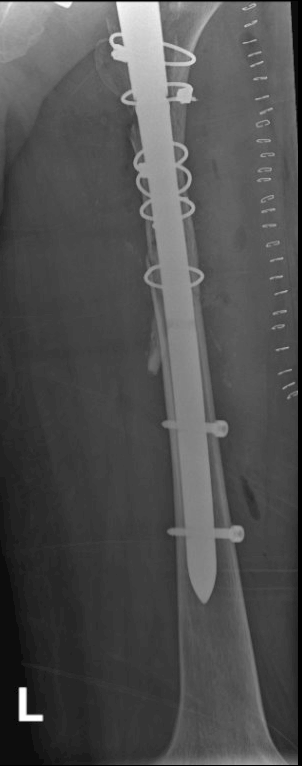

1 month post surgery

6-month follow-up